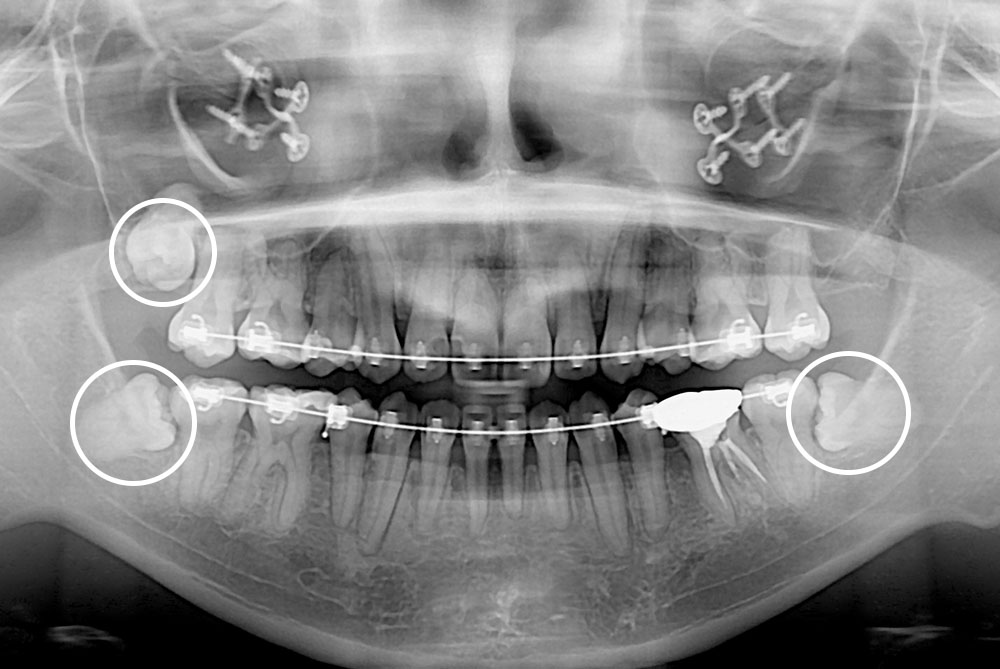

[사랑니] 매복 사랑니 발치

치료전 : 2018-08-30